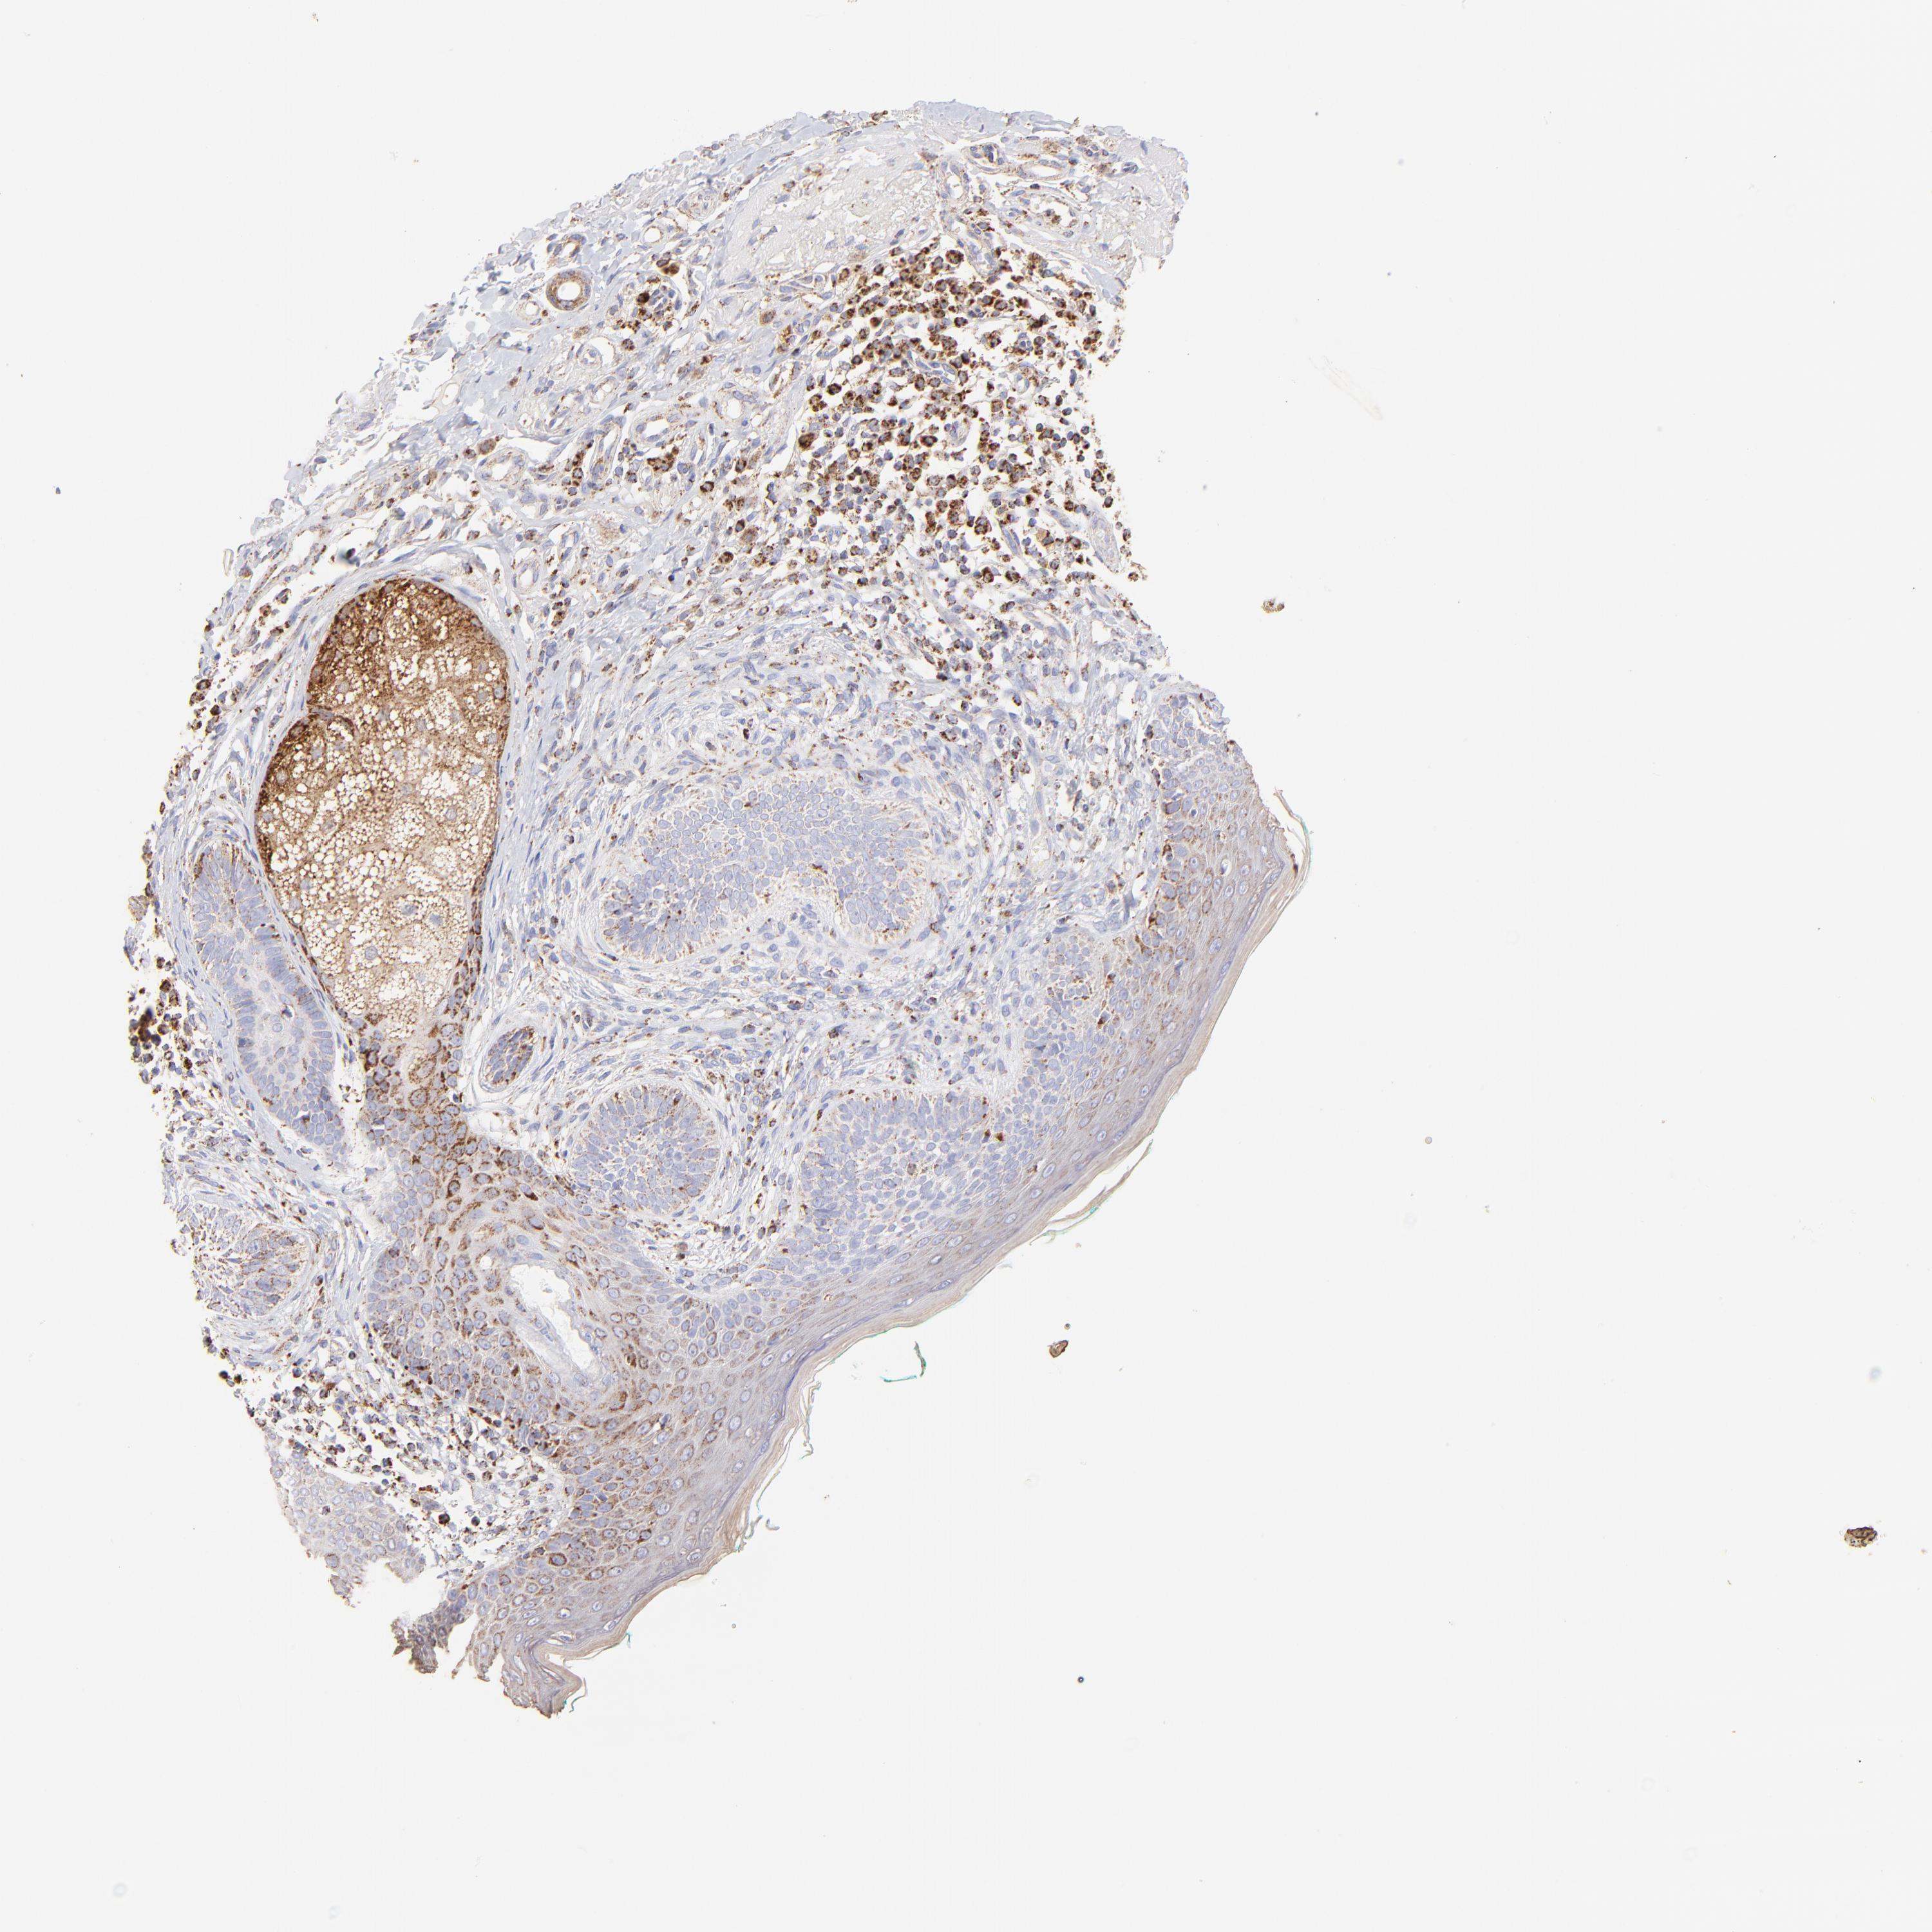

SKIN CANCER - Protein expressioni

A mouse-over function shows sample information and annotation data. Click on an image to view it in a full screen mode. Samples can be filtered based on level of antibody staining by selecting one or several of the following categories: high, medium, low and not detected. The assay and annotation is described here.

Antibody stainingi

Antibody staining in the annotated cell types in the current human tissue is reported as not detected, low, medium, or high, based on conventional immunohistochemistry profiling in selected tissues. This score is based on the combination of the staining intensity and fraction of stained cells.

Each image is clickable and will lead to virtual microscopy that enables deeper exploration of all samples and also displays staining intensity scores, fraction scores and subcellular localization as well as patient and tissue information for each sample.

Antibody HPA002907

Antibody HPA005835

Staining

High

Medium

Low

Not detected

Intensity

Strong

Moderate

Weak

Negative

Quantity

>75%

75%-25%

<25%

None

Location

Nuclear

Cytoplasmic/membranous

Cytoplasmic/membranous,nuclear

Squamous cell carcinoma, NOS

Basal cell carcinoma